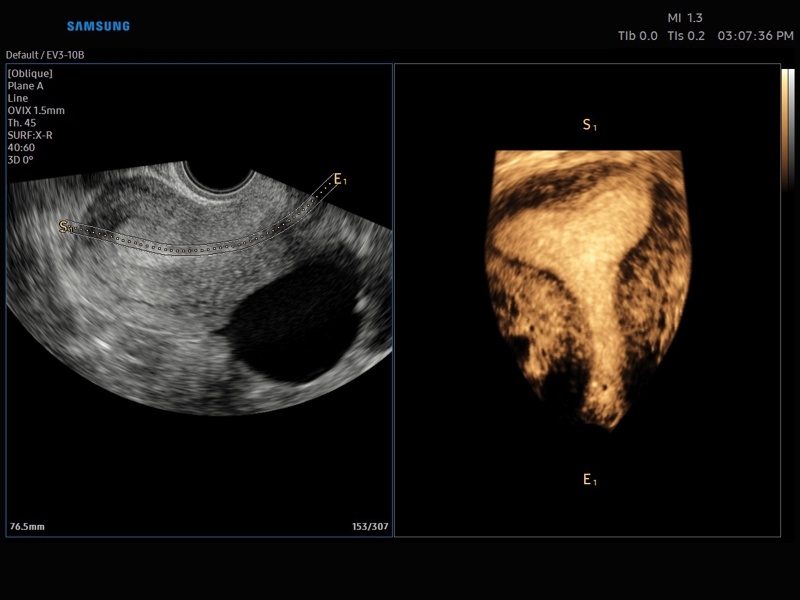

Ультразвуковой сканер V8-RUS является экспертным классом (премиальный уровень) и производится компанией Samsung Medison. Сканер V8 обеспечивает превосходное качество изображения благодаря использованию технологии Crystal Architecture™, которая включает в себя передовое аппаратное обеспечение, монокристальную технологию изготовления датчиков и сложную программную обработку ультразвуковых лучей.

• Smart 4D с технологиями Realistic VUE и Crystal VUE

• 3D - трехмерное сканирование объемными датчиками в статическом режиме в серой шкале и восстановление объемной структуры сосудов в режиме цветного / энергетического допплера (необходим Static 3D).

• Система Static 3D - трехмерное сканирование объемными датчиками в статическом режиме в серой шкале и восстановление объемной структуры сосудов в режиме цветного / энергетического допплера).

• СистемаLive 3D- трехмерное сканирование объемными датчиками в реальном масштабе времени (4D).

• OVIX(Oblique View eXtended) - получение фрагмента трехмерного изображения (в виде нескольких полупрозрачных сканов, последовательно наложенных один на другой) в направлении произвольного косого среза трехмерного объекта исследования.